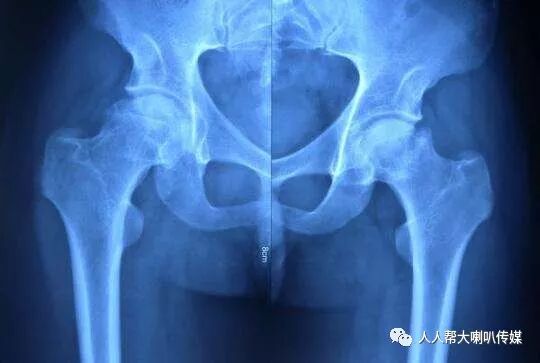

股骨头缺血性坏死,又称股骨头无菌性坏死、股骨头软骨炎、股骨头扁平症。多见于5-14岁的男童,或者30-50岁女性。引起本病的原因有:外伤后供血障碍;轻度感染致使供血障碍或骨骺生长过快;过敏反应或缺乏维生素所致。

中医认为股骨头受伤,由于病人肝肾亏虚,则筋骨失养,故见骨质坏疽,筋骨枯萎,屈伸不利。